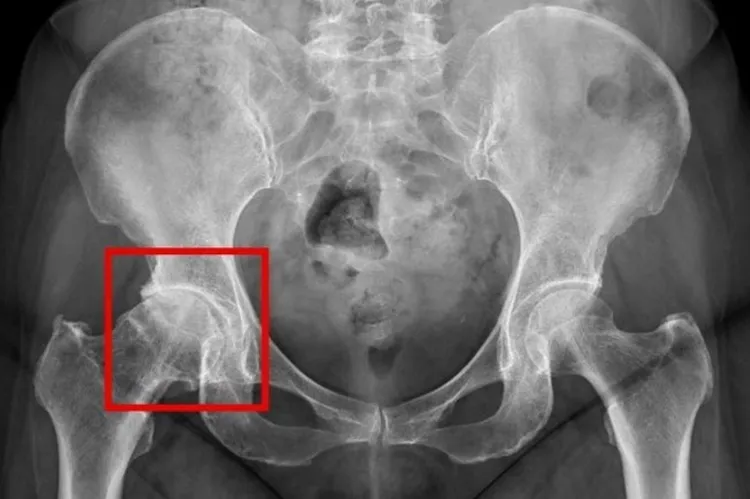

X光檢查下的退化性關節炎,紅框處可見髖關節軟骨磨損嚴重,導致骨頭間縫隙狹窄、引發發炎與疼痛。台北慈濟醫院提供

骨科醫師黃振文說明,髖關節是人體重要的負重關節,由骨盆與大腿骨組成,表面有軟骨可減少摩擦、吸收衝擊。一旦軟骨因老化或磨損受損,骨頭直接接觸就會引發發炎與疼痛。初期通常在活動時才會痛,但隨著病情加重,連休息或夜間也可能持續疼痛,常見症狀包含鼠蹊部、大腿內側或下背痛,甚至出現關節卡卡聲與跛行。